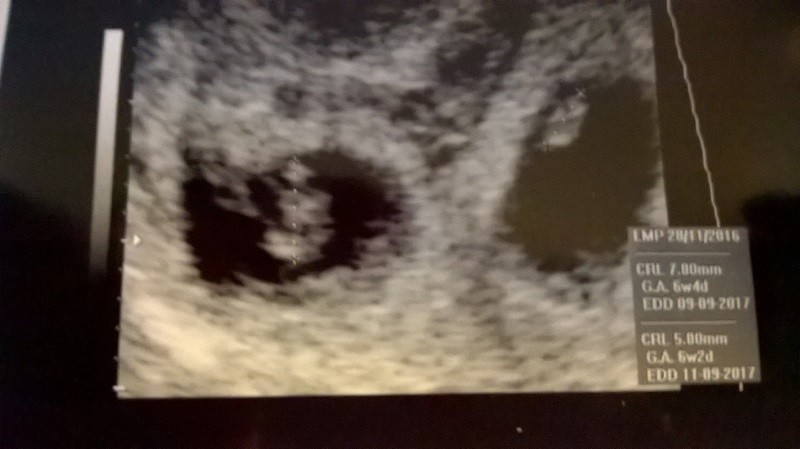

Poniżej fasolinek 1 :

i fasolinek 2: